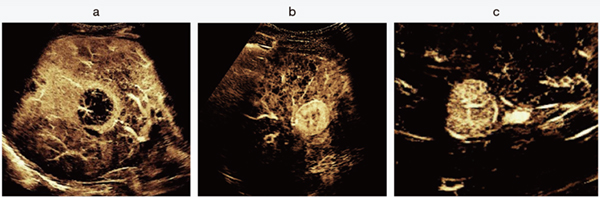

〔Super Resolution MVIの臨床画像〕

図1 正常肝実質のSuper Resolution MVI画像

門脈の末梢が精緻に描出されており,門脈に並走する肝動脈も明瞭に分離して観察される。肝実質が時間の経過とともに規則的かつ均一に染まり,正常な肝血流動態を反映している。

a:Flash後1秒 b:Flash後3秒 c:Flash後7秒

図2 Super Resolution MVIによる肝腫瘍の血管構築パターン

a:転移性肝がん b:肝細胞がん c:限局性結節性過形成